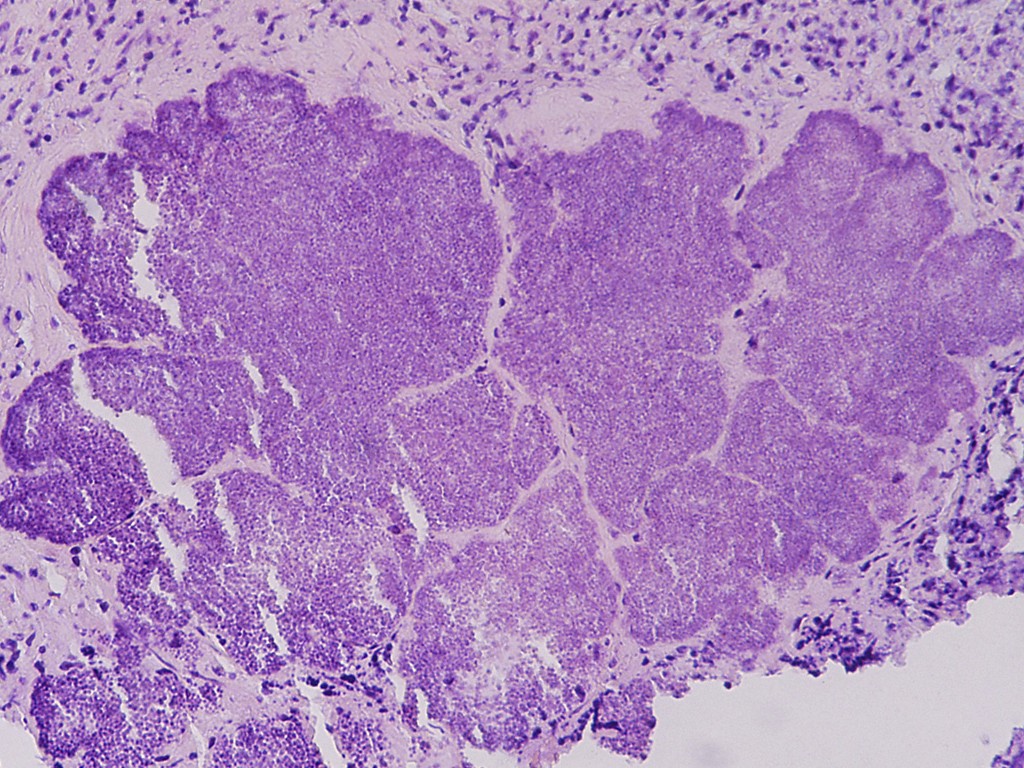

![Job syndroom, hyper IgE syndroom (click on photo to enlarge) [source: www.huidziekten.nl] Job syndroom, hyper IgE syndroom](../../../images/hyper-IgE-syndroom-1z.jpg) |

![Job syndroom, hyper IgE syndroom (click on photo to enlarge) [source: www.huidziekten.nl] Job syndroom, hyper IgE syndroom](../../../images/hyper-IgE-syndroom-2z.jpg) |

| Job (hyper

IgE) syndroom |

koude

abces bij Job syndroom |

![Job syndroom, hyper IgE syndroom (click on photo to enlarge) [source: www.huidziekten.nl] Job syndroom, hyper IgE syndroom](../../../images/hyper-IgE-syndroom-3z.jpg) |

![Job syndroom, hyper IgE syndroom (click on photo to enlarge) [source: www.huidziekten.nl] Job syndroom, hyper IgE syndroom](../../../images/hyper-IgE-syndroom-4z.jpg) |

| koude

maldentitie

bij Job syndroom |